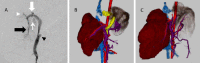

Fig. 2

Transverse computed tomography images of a two-year-old female Shih tzu dog before surgical treatment. (A): Dorsal–ventral abdominal radiograph. Three lines reveal each transverse section level. Transverse computed tomography images at levels of (B) the tenth, (C) the eleventh and (D) the twelfth thoracic vertebrae in the portal phase revealed an enlarged bile duct (large arrow: blue) and gallbladder (arrowhead: red) and a shunt vessel (small arrow: yellow) between the caudal vena cava and left gastric vein. No left liver parenchyma was observed at any transverse section levels.

Fig. 3

Computed tomography multiplanar reconstruction (MPR) images of a two-year-old female Shih tzu dog before surgical treatment. (A): Sagittal MPR image. Three lines reveal each dorsal section level. (B-D): Dorsal MPR images reveal that the greater part of the left diaphragm is attached to the stomach and the remaining liver exists only on the right side of the gallbladder. Large arrow (blue) shows spleen, small arrow (yellow) shows pancreas, large arrowhead (red) showed bile duct and small arrowhead (red) shows the gallbladder. No left liver parenchyma was observed at any dorsal section levels.